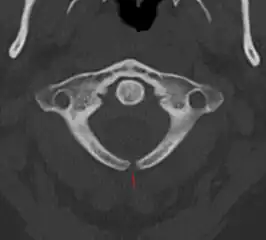

X-ray image of spina bifida occulta in S-1

X-ray image of spina bifida occulta in S-1 X-ray computed tomography scan of unfused arch at C1